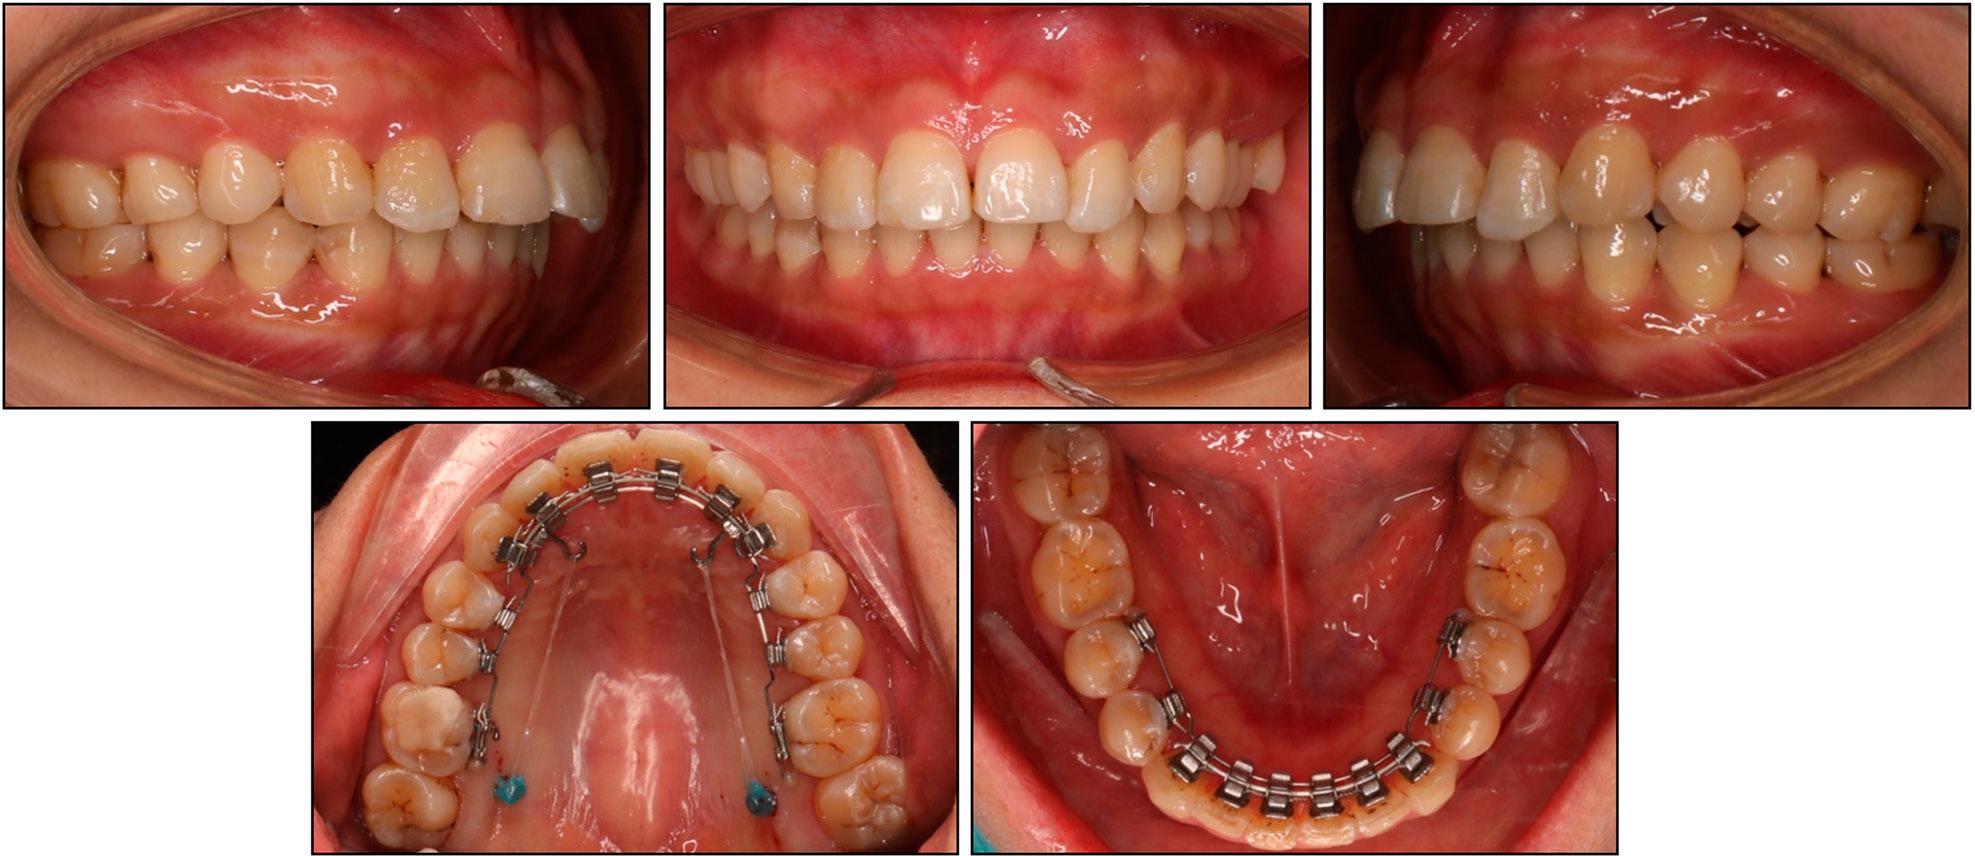

Cephalometric measurements

| Pretreatment | Posttreatment | |

|---|---|---|

| Skeletal | ||

| SNA (°) | 85.7 | 84.8 |

| SNB (°) | 79.6 | 80.1 |

| ANB (°) | 6.1 | 4.7 |

| FMA (°) | 20.0 | 20.5 |

| Dental | ||

| U1-SN (°) | 80.3 | 92.4 |

| U1-PP (°) | 89.2 | 101.1 |

| U1-NA (°) | -5.5 | 7.6 |

| U1-NA (mm) | -3.4 | -1.2 |

| IMPA (°) | 94.2 | 95.1 |

| L1-NB (°) | 22.1 | 22.7 |

| L1-NB (mm) | 2.8 | 3.1 |

| Interincisal angle (°) | 157.3 | 144.9 |

| Upper incisal display (mm) | 5.8 | 3.8 |

| Soft tissue | ||

| E-line/UL (mm) | -0.7 | -0.9 |

| E-line/LL (mm) | -1.2 | -1.2 |